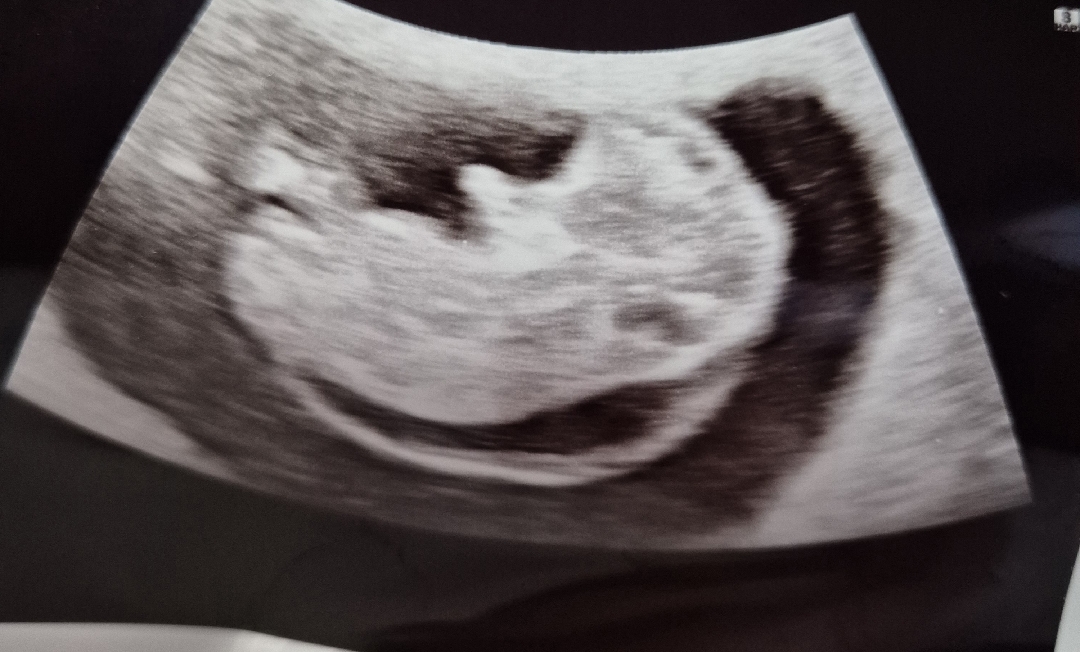

안녕하세요! 10주차 검진가서 초음파를했는데 물이고였다며 비정상소견이라고 2주뒤 검사해보고 비교해보자는데 너무 답답하네요ㅜㅜ 혹시 비슷한경험이라던가 조언해주실분 계신가요?

사진만 봐서는 목덜미투명대가 두꺼워 보이게 찍혀있네요.. 1차 기형아 검사때 다시 확인하셔야겠어요